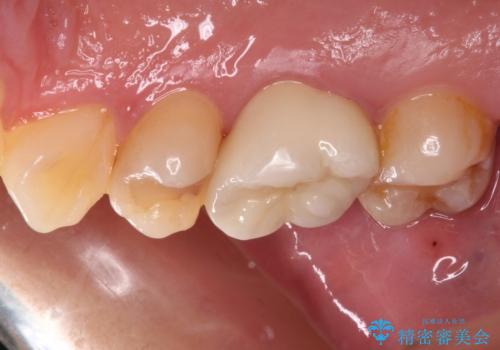

セラミッククラウンを装着する前に仮歯を装着しましたが、その時点で強い痛みはほぼ改善され、セラミッククラウン装着後には痛みはもちろん、しみる症状も感じることがなくなりました。